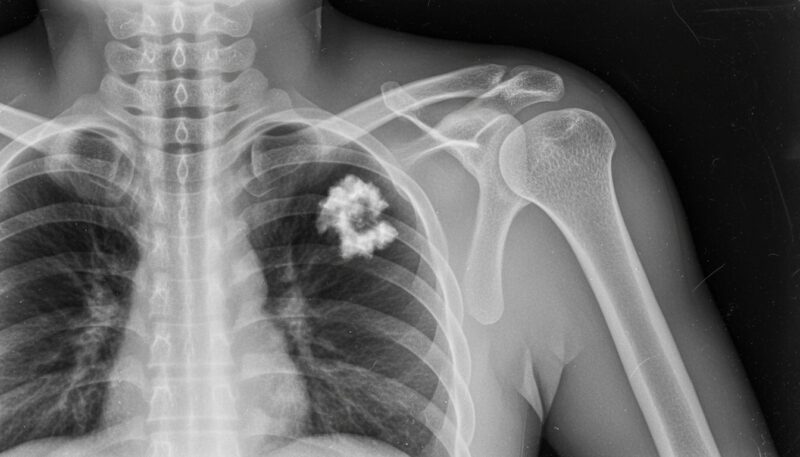

石灰沈着性腱板炎の特徴

石灰沈着性腱板炎は、特に40〜50代の女性に多い疾患です。

肩関節周囲の腱板にリン酸カルシウムの結晶(石灰)が沈着して生じます。沈着の原因は明らかになっていませんが、肩を上げる腱(腱板)の内に石灰が付着し、夜間などに急に肩の痛みが生じ、肩が動かせなくなる病気です。

症状の経過は肩関節周囲炎に類似しており、急性期と慢性期で治療法が異なるため、病態把握や正確な診断が重要です。診断は、関節の痛みの部位や関節の動きの制限を見る診察とレントゲンで腱板に石灰が付着しているのを確認します。詳細な検査として、他の病気との判別に、MRIなどを行うことがあります。

安静時や夜間にも強い痛みが続くため、肩を動かすこと自体が難しくなります。まずは安静を取りながらも症状の改善に向けたさまざまな治療アプローチが必要となります。四十肩や五十肩と似たような症状が起きるのが特徴的ですが、レントゲンで石灰の沈着が確認できるため、正確な診断が可能です。